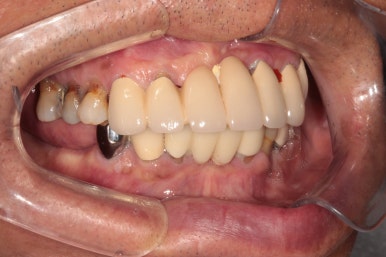

우측 어금니를 보시면, 너무나 많은 치석으로 인해 만성치주염에 시달렸던 치아들은 사라지고, 이제 깔끔하게 임플란트로 대체된 것을 보실 수 있습니다.

임플란트는 보통 1 piece로 제작되기 때문에, 기존에 흔들리고 잇몸이 올라가버린 어금니보다 오히려 음식도 덜 끼고.. 사용하기 상당히 좋은 환경이 조성되었지요.

좌측 어금니 또한 깔끔하게 그럴싸하게!! 본인치아와 흡사한 형태로 제작해드렸습니다.

사실 처음에 잇몸 염증으로 고름이 가득 차있던 왼쪽 아래 송곳니 부위에는 임플란트 심는 것 자체가 불가능 했습니다만, 인접한 자리에 임플란트를 심어내어 마치 임플란트가 있는 것 같이 깔끔하게 제작 완료!